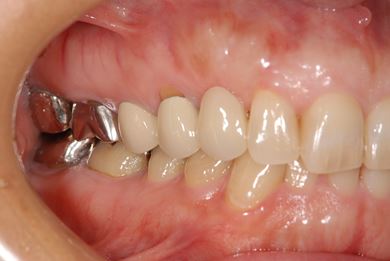

治療前

• 治療前